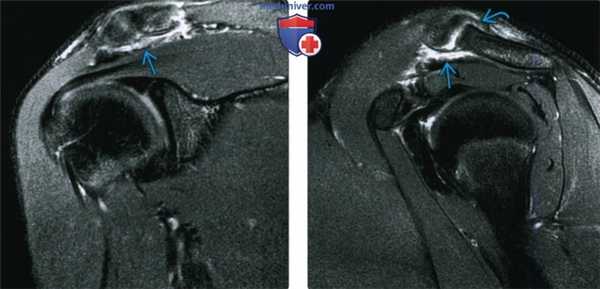

(Слева) Фронтальная косая МРТ Т2ВИ FS: пациент с I типом акромиально-ключичного вывиха после падения на область плечевого сустава. Отмечается отек вокруг акромиально-ключичного сустава без расширения сустава.

(Справа) На сагиттальной косой МРТ Т2ВИ FS у этого же пациента тоже виден отек вокруг акромиально-ключичного сустава и частичный разрыв суставной капсулы. Такие данные у пациента с болью и напряжением вокруг акромиально-ключичного сустава после травмы без расширения сустава соответствуют I типу акромиально-ключичного вывиха.

4. МРТ при травме акромиально-ключичного сустава:

• Т1 ВИ:

о Расширенный акромиально-ключичный сустав или приподнятый дистальный конец ключицы

о Разрыв акромиально-ключичной и клювовидно-ключичной связки

• Т2 ВИ FS:

о Отек мягких тканей вокруг акромиально-ключичного сустава

о Суставной выпот

о Отек костного мозга, прилежащего к суставу